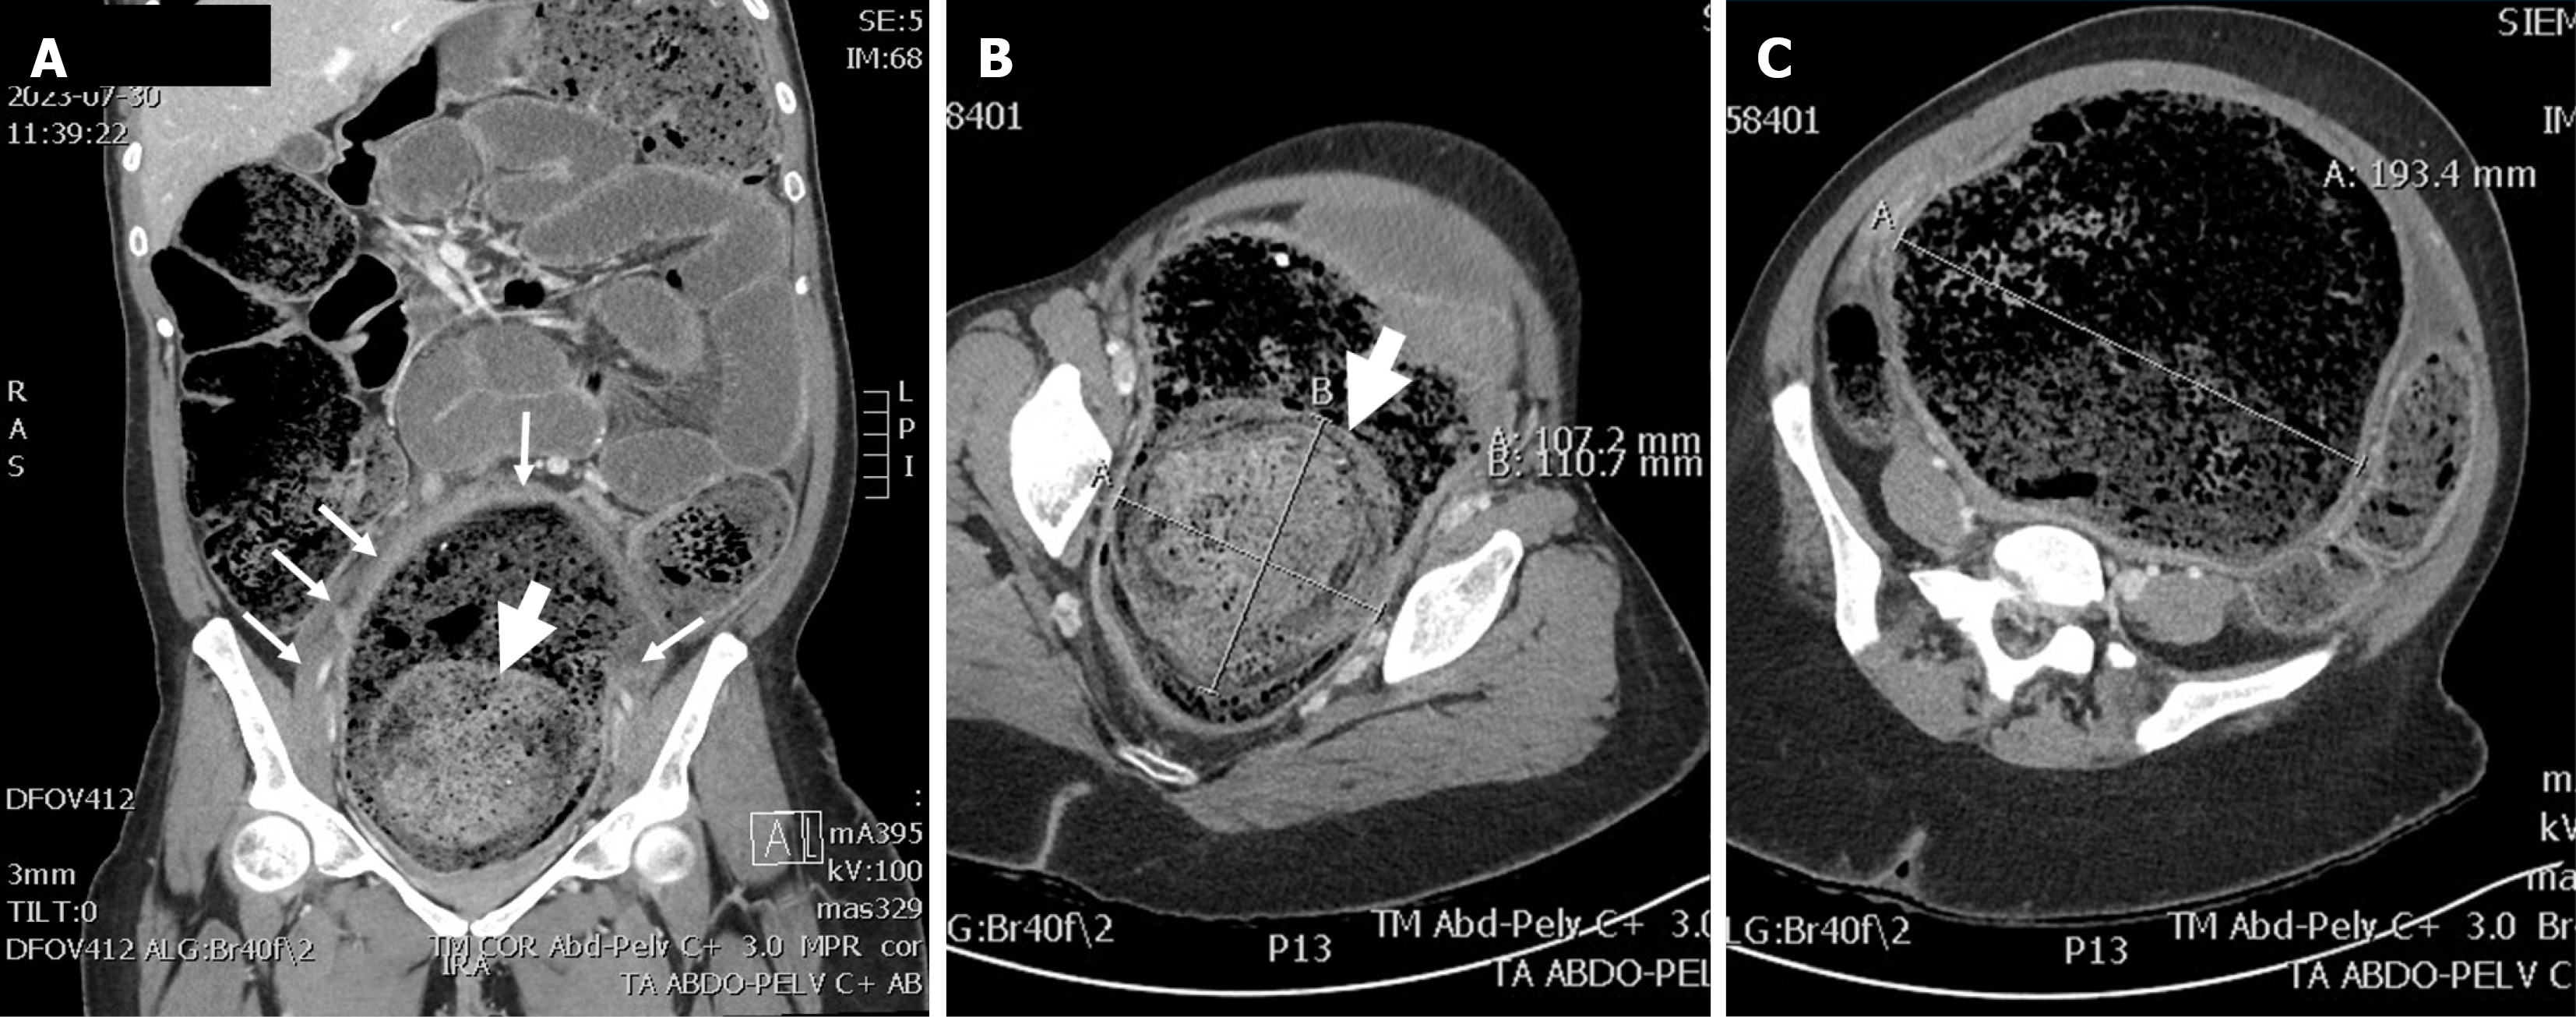

Figure 1 Plain film showing huge accumulation of stools.